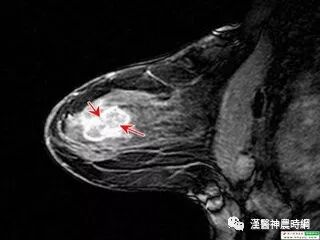

女性乳腺是由皮肤、纤维组织、乳腺腺体和脂肪组成的,乳腺癌是发生在乳腺腺上皮组织的恶性肿瘤。乳腺癌中99%发生在女性,男性仅占1%。

乳腺并不是维持人体生命活动的重要器官,原位乳腺癌并不致命;但由于乳腺癌细胞丧失了正常细胞的特性,细胞之间连接松散,容易脱落。癌细胞一旦脱落,游离的癌细胞可以随血液或淋巴液播散全身,形成转移,危及生命。目前乳腺癌已成为威胁女性身心健康的常见肿瘤。

80%的乳腺癌患者以乳腺肿块首诊。患者常无意中发现乳腺肿块,多为单发,质硬,边缘不规则,表面欠光滑。大多数乳腺癌为无痛性肿块,仅少数伴有不同程度的隐痛或刺痛。